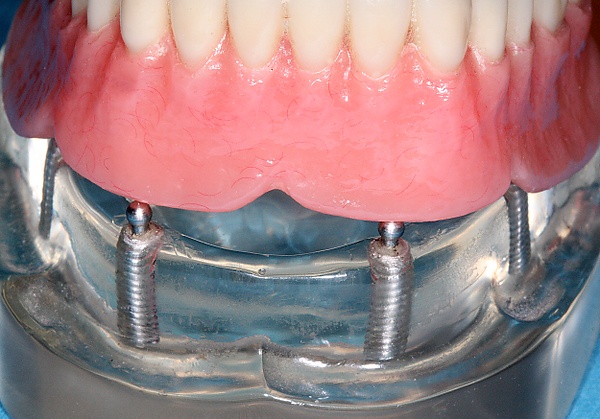

- имплантация All-on-4 («все на 4») — это зубопротезирование полного зубного ряда методом имплантации четырех искусственных корней (имплантатов) в костную ткань челюсти пациента с последующей установкой на них протеза.[1]

- создать дополнительную опору и установить несъёмный протез;

- создать опору для улучшения фиксации съёмного протеза;